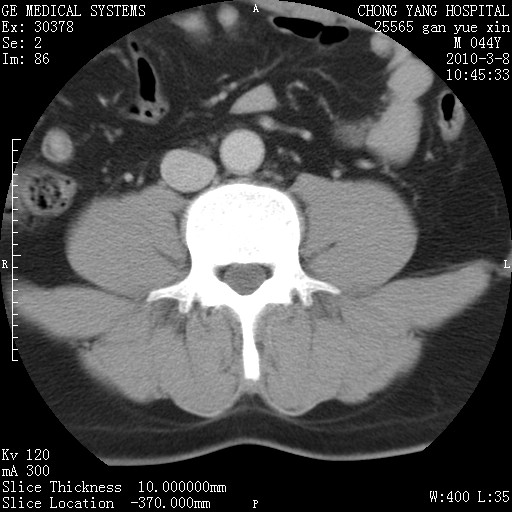

标题: CT24940:主动脉增强,典型病例。 [打印本页]

标题: CT24940:主动脉增强,典型病例。

夹层动脉瘤。

动脉夹层

夹层动脉瘤,典型

主动脉夹层。

动脉夹层的分型:

⒈debakey分型:根据主动脉夹层累及部位,分为三型:ⅰ型:原发破口位于升主动脉或主动脉弓部,夹层累及升主动脉、主动脉弓部、胸主动脉、腹主动脉大部或全部,少数可累及髂动脉。ⅱ型:原发破口位于升主动脉,夹层累及升主动脉,少数可累及部分主动脉弓。ⅲ型:原发破口位于左锁骨下动脉开口远端,根据夹层累及范围又分为ⅲa,ⅲb。ⅲa型:夹层累及胸主动脉。ⅲb型:夹层累及升主动脉、腹主动脉大部或全部。少数可累及髂动脉。

⒉stanford分型:a型:夹层累及升主动脉,无论远端范围如何。b型:夹层累及左锁骨下动脉开口以远的降主动脉。

夹层动脉瘤,少量胸水

夹层动脉瘤;左侧少量胸腔积液。

典型主动脉夹层。